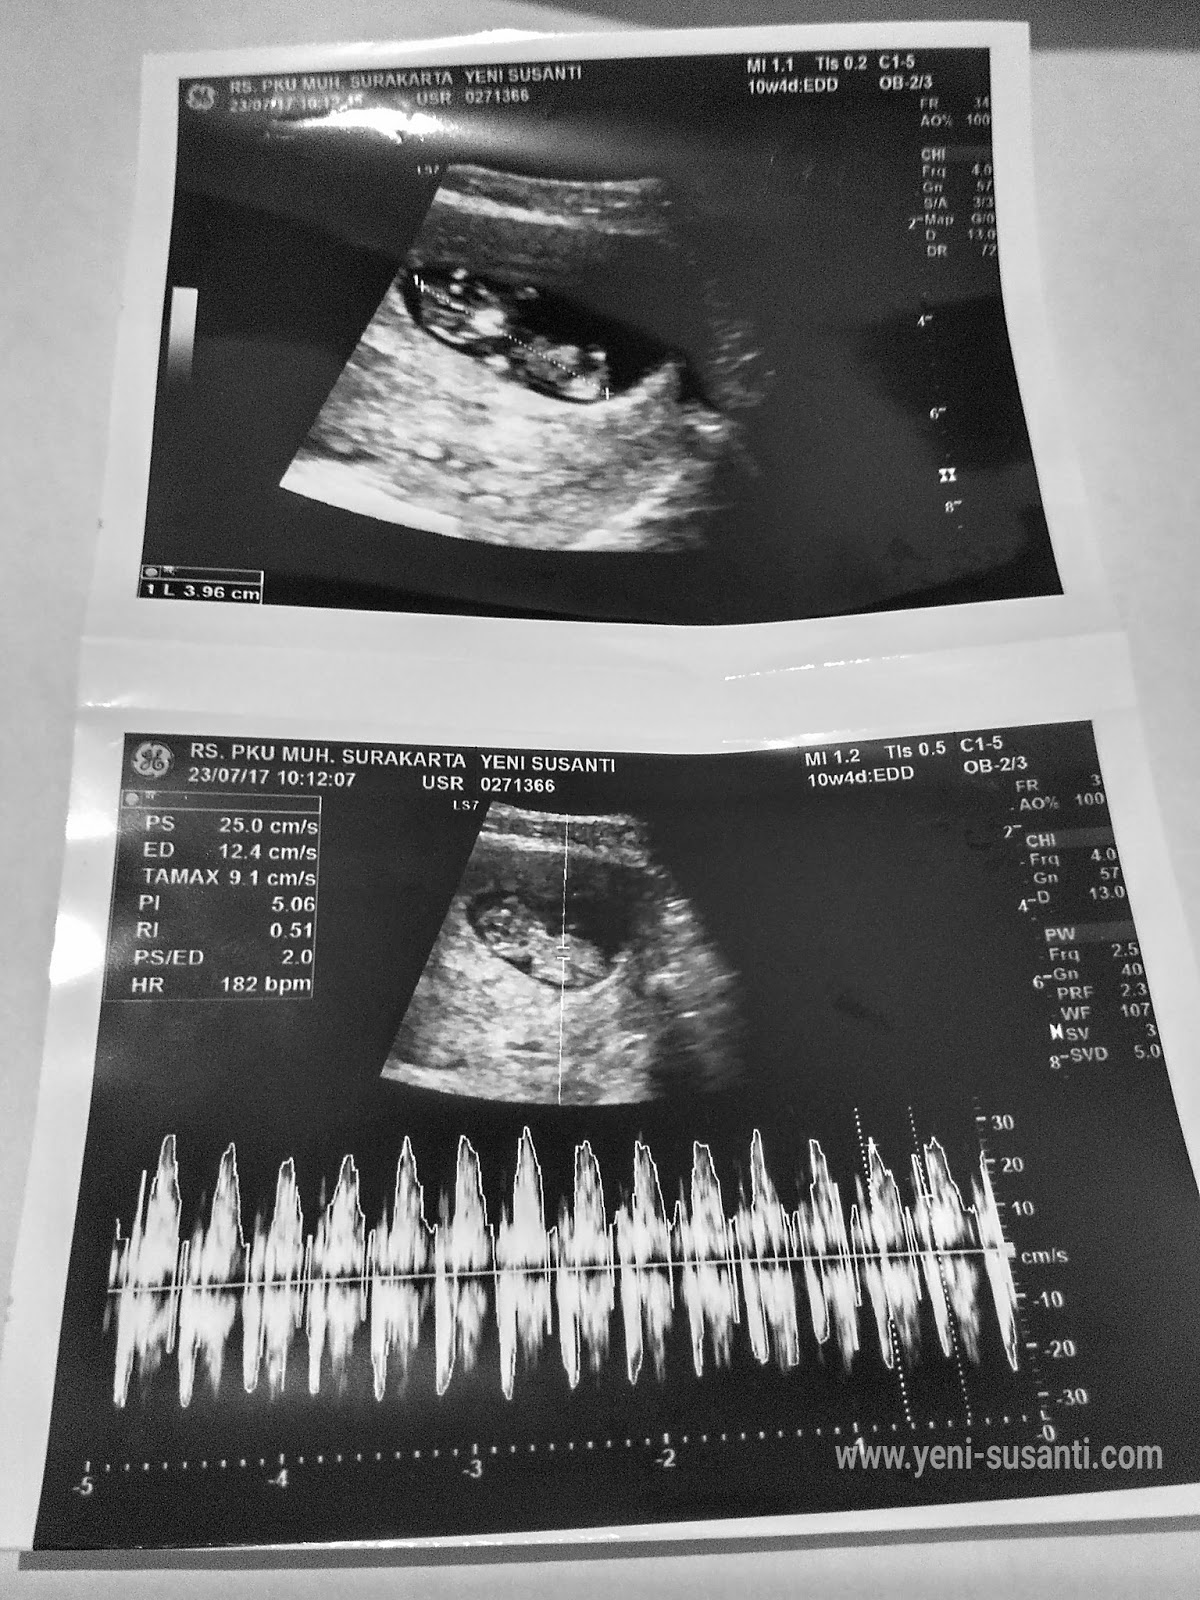

Makin hari rasanya tubuhku aneh, aku jadi gampang lelah, mual-mual dan sering sensitif. Kembali menemui dokter Obgyn adalah pilihan yang aku ambil dan saat di USG hasilnya, taraaa..... ada kantong kehamilan di rahimku. Subhanallah, Allah menggantikan apa yang telah diambilNya begitu cepat. Tuhan kembali mempercayakan amanah besar kepadaku.

Satu kalimat yang diucapkan Spog-ku saat pertama kali aku periksa dan selalu aku tanamkan dalam hati dan pikiranku adalah "Tidak ada obat yang mampu mempertahankan kehamilan yang penuh resiko ini kecuali doa dan sedekah". Aku selalu menitikkan air mata tiap mengingat kalimat itu, syukur penuh haru atas kehamilan ketiga ini. Sekarang usia kehamilanku sudah hampir memasuki trisemester ke dua. Semoga semua normal hingga waktunya dia lahir. Amiin !

![]() |

| Hamil lagi pasca kuret tanpa melewati siklus haid |